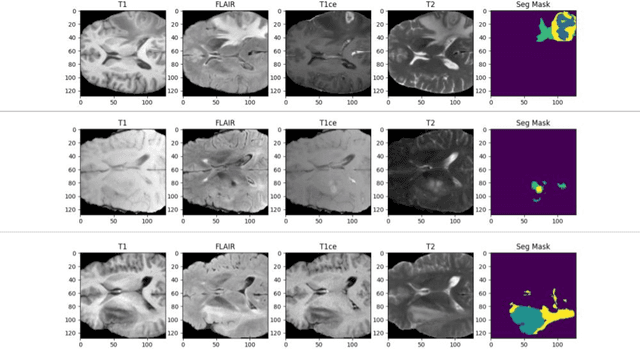

Cancer remains one of the leading causes of mortality worldwide, and among its many forms, brain tumors are particularly notorious due to their aggressive nature and the critical challenges involved in early diagnosis. Recent advances in artificial intelligence have shown great promise in assisting medical professionals with precise tumor segmentation, a key step in timely diagnosis and treatment planning. However, many state-of-the-art segmentation methods require extensive computational resources and prolonged training times, limiting their practical application in resource-constrained settings. In this work, we present a novel dual-decoder U-Net architecture enhanced with attention-gated skip connections, designed specifically for brain tumor segmentation from MRI scans. Our approach balances efficiency and accuracy by achieving competitive segmentation performance while significantly reducing training demands. Evaluated on the BraTS 2020 dataset, the proposed model achieved Dice scores of 85.06% for Whole Tumor (WT), 80.61% for Tumor Core (TC), and 71.26% for Enhancing Tumor (ET) in only 50 epochs, surpassing several commonly used U-Net variants. Our model demonstrates that high-quality brain tumor segmentation is attainable even under limited computational resources, thereby offering a viable solution for researchers and clinicians operating with modest hardware. This resource-efficient model has the potential to improve early detection and diagnosis of brain tumors, ultimately contributing to better patient outcomes